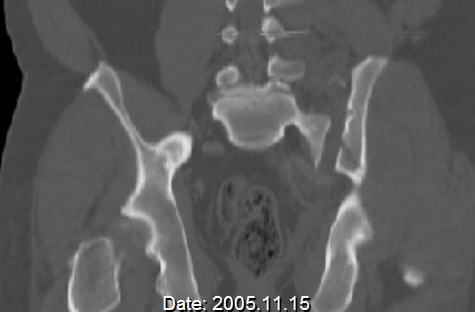

Re: APC III pelvis fx

Request for more images.. Axial and coronal recon (pt in binder.)

Haven't posted initial AP pelvis as it is poor quality, non digital film.